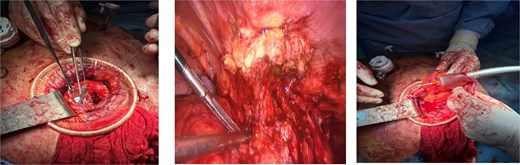

The patient underwent laparoscopic revision. Working trocars were placed, and pneumoperitoneum was established. Intraoperatively, an inflammatory mass with adhesions to the anterior abdominal wall was identified at the previous laparotomy site. Careful adhesiolysis was performed, preserving viable tissue, and the cecum was freed from its attachment to the prior McBurney incision. The terminal ileum and ascending colon were mobilized. A relaparotomy was then performed through the previous incision, and a wound protector was placed to exteriorize the inflammatory block. The terminal ileum was transected 15 cm proximal to the ileocecal valve, and the ceco-ascending colon was divided just above the pathological segment. An extracorporeal side-to-end ileocolic anastomosis was constructed using a circular stapler (Fig. 2). Peritoneal lavage was performed, hemostasis was verified, and a drain was placed through one of the ports. The abdominal wall at the relaparotomy site was repaired, and four primary-delayed skin sutures were placed with a Betadine-soaked gauze. The procedure was completed without intraoperative complications.